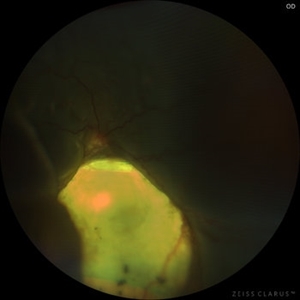

Total Rhegmatogenous retinal detachment with opened posterior margin of lattice degeneration

Jul 18 2023 by Harsh Vardhan Singh, MS

78-year-old man with history of defective following cataract surgery showed total retinal detachment on examination

Photographer: Harsh Vardhan Singh, AIIMS, Guwahati

Imaging device: Zeiss Clarus 700

Condition/keywords: chronic retinal detachment, peripheral lattice degeneration, rrd